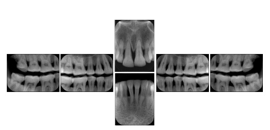

2. A patient requests cosmetic surgery to enhance their facial appearance. The case requires consultation between an orthodontist in New York and an oral surgeon in California. The cephalometric series of 2D projections constructed from a volumetric CT data set that is used for the discussion is arranged by a Structured Display for transfer between the two practitioners.

Cephalometric Series Structured Display

Figure OO-2. Cephalometric Series Structured Display